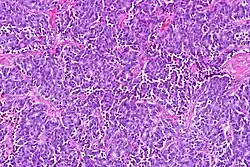

| Atypical pulmonary carcinoid. H&E stain. | |

Atypical carcinoid tumors have increased mitotic activity (2-10 per 10 HPF), nuclear pleomorphism or foci of necrosis.